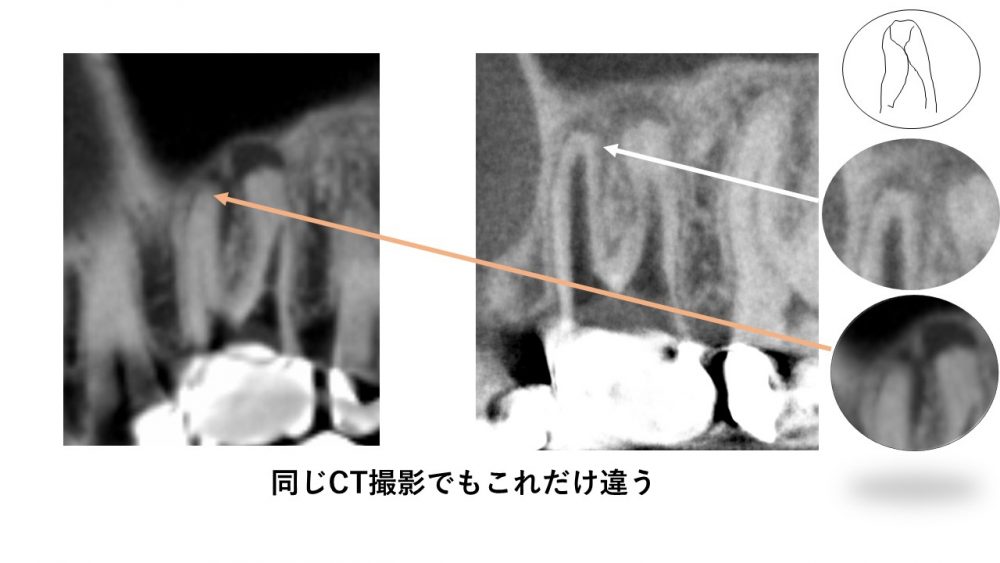

同じCTでもこれだけ違う

CT撮影をすれば、根の治療が治りやすいのはもちろんです。

しかし、残念ながらそのCTも機種によって解像度が全く異なります。

中には被爆量が少ないことをうたい文句にしている機種があるのですが、被爆量が少ないということは、実はそれだけ情報が少なくなるということなのです。情報を得るために必要な被爆量を減らしてしまえば、撮影自体の意味がなくなってしまいます。

下の写真は、外注で撮影したCTと当医院で使用している同じ場所のCT写真ですが、解像度が全く違ういます。

根管治療で、詳細な根の状態を確認するために、外注撮影したCT写真ですが、根管がはっきり映っていなかったので当医院で撮影しなおしたものです。

実は低被爆を歌いながら治療に意味のない撮影になってしまっていることも少なくないので、気をつけなければなりません。

顕微鏡を使って、治りが悪い根の治療をする場合、根管の位置を探る必要があります。その際正確な3次元的根管の位置や形態がわかることは非常に重要なことなのです。

CT撮影もモードがあり、全体を撮影するモードと詳細を撮影するモードがあります。

歯のCT撮影の場合、医科のCTと比べスライス幅を非常に細かくするる必要があります。当医院のCTでは詳細モードでは65μmで撮影するため、詳細な3次元の根の構造を撮影することが可能です。